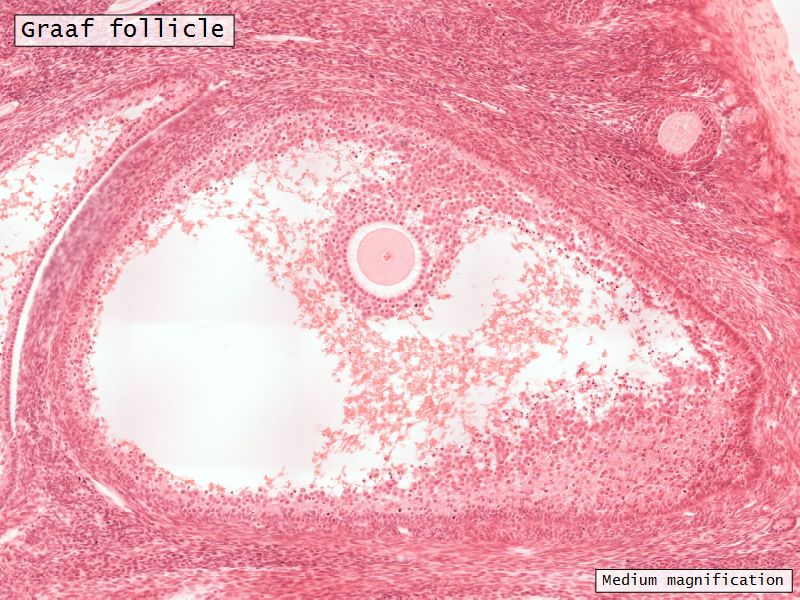

Follicular maturation

- Primordial follicle

- Growing follicle

- Primary follicle

- Secondary follicle

- Mature follicle (Graafian)

Components of a follicle

- Theca

- externa

- interna

- basal lamina

- Granulosa cells

- Antrum

- Cumulus oophorus >> Corona radiata

- Oocyte